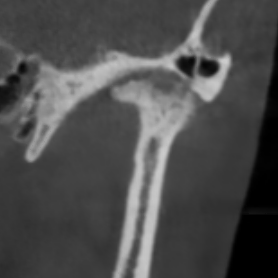

У здорового височно-нижнечелюстного сустава суставные поверхности гладкие и ровные. Такие суставы, как правило, восстанавливаются быстро.

Но, ко мне приходят пациенты с изменёнными суставными поверхностями в виде артроза. Эти суставы повреждены, и в них нарушено нормальное вращение.